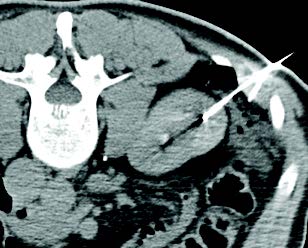

Cryoablation needle trajectory angled to protect critical kidney structure Cryoablation needle trajectory angled to protect critical kidney structure

Using the Trajectory of the Needle to Protect Critical Structures

A 53-year-old man presented with 2.5 cm x 2.3 cm endophytic RCC  in the anterior aspect of the lower pole of the left kidney. Cryoablation was performed with one IceForce™ 2.1 CX Needle. The tip of the needle was pointed toward the ureter since lethal ice only extends 5 mm beyond the tip of the needle. The patient was discharged the same day and follow-up imaging demonstrated no residual or recurrent disease 12-months post ablation.

AJ Gunn, MD I University of Alabama at Birmingham I Birmingham, AL